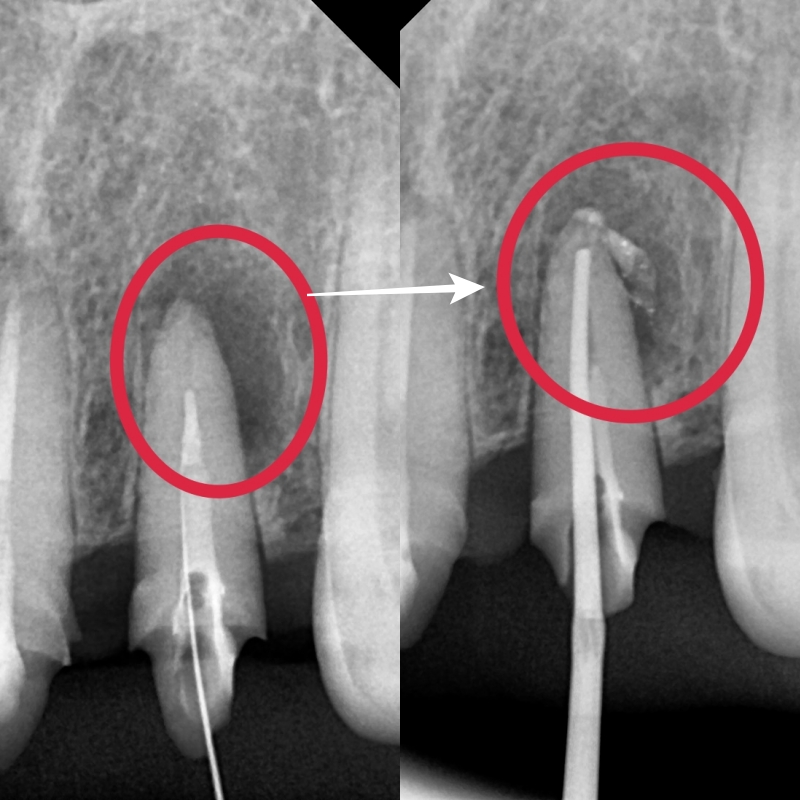

제거하고 엑스레이를 찍었을 때 4개 중 하나의 치아가 뿌리끝에 염증이 잡혀있는 것을 확인할 수 있었습니다

기존 치료된 치아의 재 신경치료

염증 때문에 뿌리끝에 어둡게 보이는 부분은 주변 뼈가 녹아 있다는 뜻입니다.

기존 재료를 깨끗하게 제거한 후 여러 번 치료를 진행한 끝에

오른쪽 사진을 보면 염증소견이 가라앉았고, 뿌리 주변부를 약재가 감싸주는 사진을 확인할 수 있었습니다.

치아 뿌리의 상태가 아주 건전하지는 않았지만 이 정도의 치료 결과를 보았을 때는

조금 더 자연치아를 유지할 수 있다고 판단하고 보철 치료를 진행했습니다.